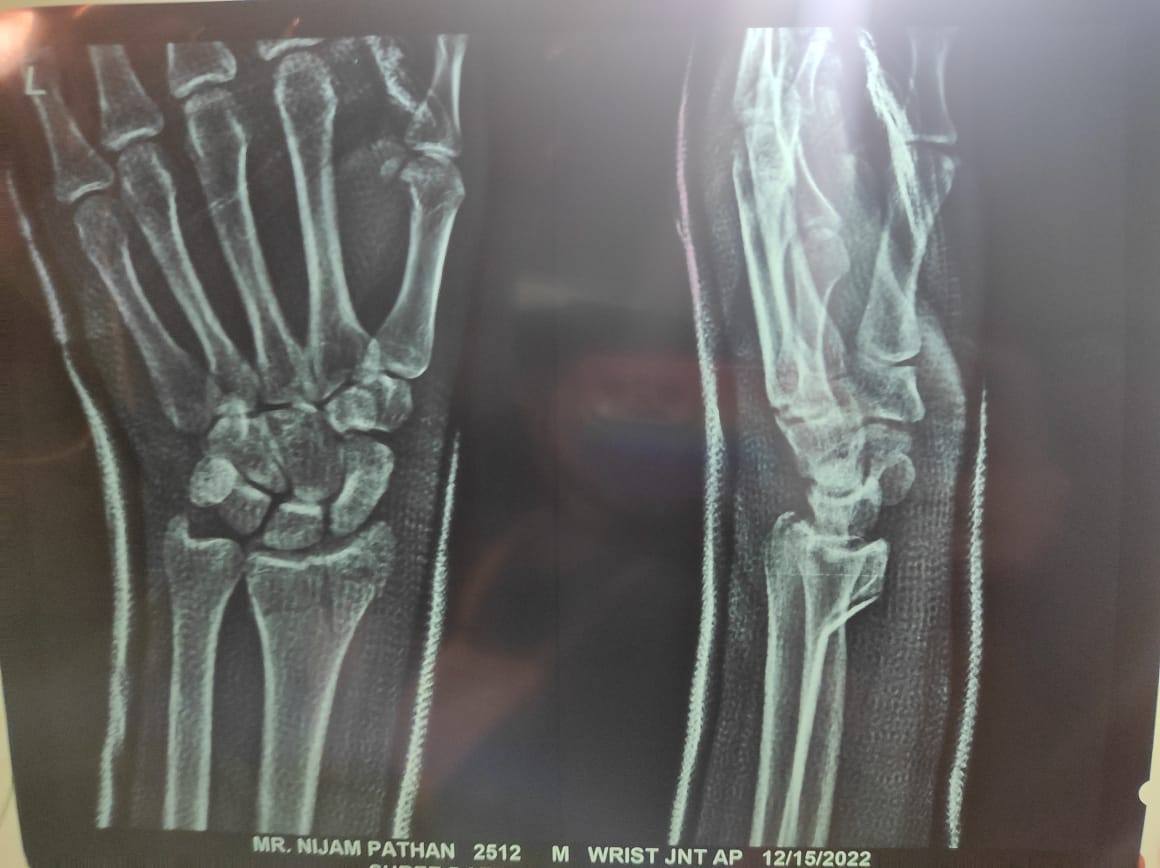

Nijam Pathan

. Following